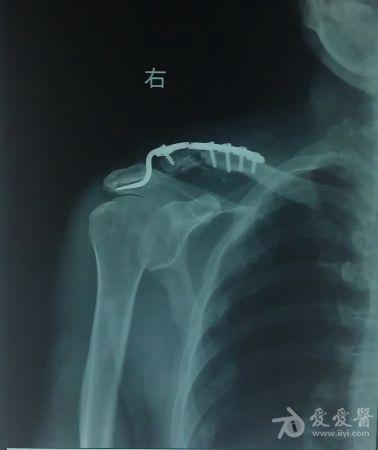

锁骨钩钢板内固定材料,术后复查X

线片:右锁骨远端骨折术后,对位对线良好,钢板位置良好(图片二)。手术成功,顺利出院,治疗过程并得到患者及家属的肯定。患者陈XX于2012